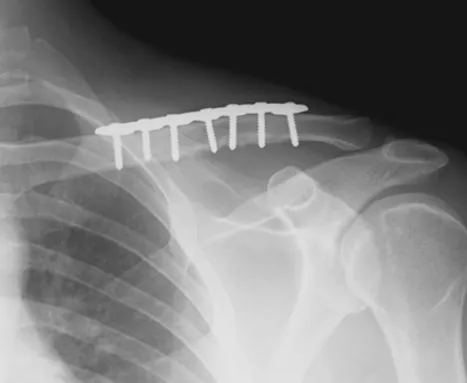

鎖骨骨折 之併發症 後遺症 建議與治療 – 松山景能物理治療所

2025/10/22鎖骨骨折 手術的方式會因患者的情況、骨折部位和骨折程度等因素而有所不同,一般有以下幾種手術方式:

以上三種手術方式各有優缺點,具體選擇哪種手術方式需要根據患者的骨折情況和病情進行綜合評估 -